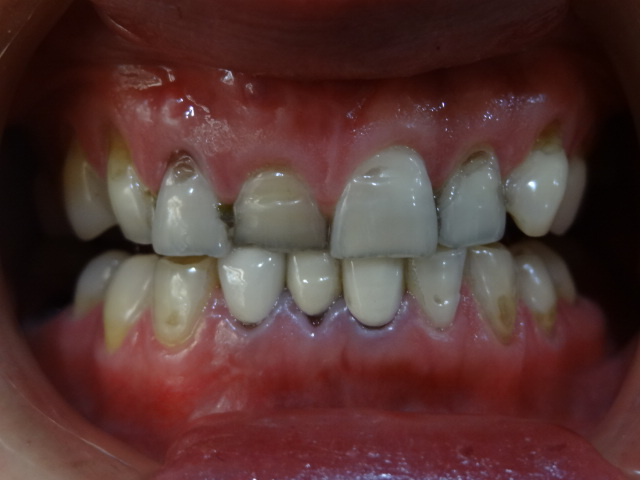

自己的牙齒有些畸形,所以想通過做牙齒矯正的方式來進(jìn)行改善,想問問紹興牙齒矯正大概多少錢?牙齒正畸的費用一般是多少?

紹興牙齒正畸的費用,大概是在1萬元到15,000元左右的,主要是根據(jù)每個患者的牙齒畸形情況來進(jìn)行決定的,如果畸形的情況特別的嚴(yán)重,那么可能費用也會更高一些,另外牙齒正畸的話,主要是通過佩戴牙套的方法來進(jìn)行改善的,佩戴牙套的時間,可能是需要一年到一年半左右的時間。正畸時期要注重口腔的衛(wèi)生,注重個人的飲食等。